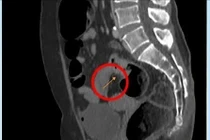

Một bệnh nhân nghi ngộ độc nấm đang được điều trị tại Bệnh viện Đa khoa vùng Tây Nguyên. (Ảnh baovephapluat/vn)

Do bị ngộ độc nặng nên 3 trong 7 bệnh nhân đã được Trung tâm Y tế huyện Lắk chuyển lên Bệnh viện Đa khoa vùng Tây Nguyên.

Theo Bác sĩ Khoa Hồi sức tích cực - Chống độc, Bệnh viện Đa khoa vùng Tây Nguyên cho biết, 3 bệnh nhân có tình trạng đau bụng, nôn ói, đau đầu, chóng mặt, chẩn đoán ngộ độc nấm không rõ loại.

Trong 3 bệnh nhân nhập viện, có bệnh nhân bị tổn thương gan, tổn thương thận nên đang được tích cực theo dõi, điều trị.